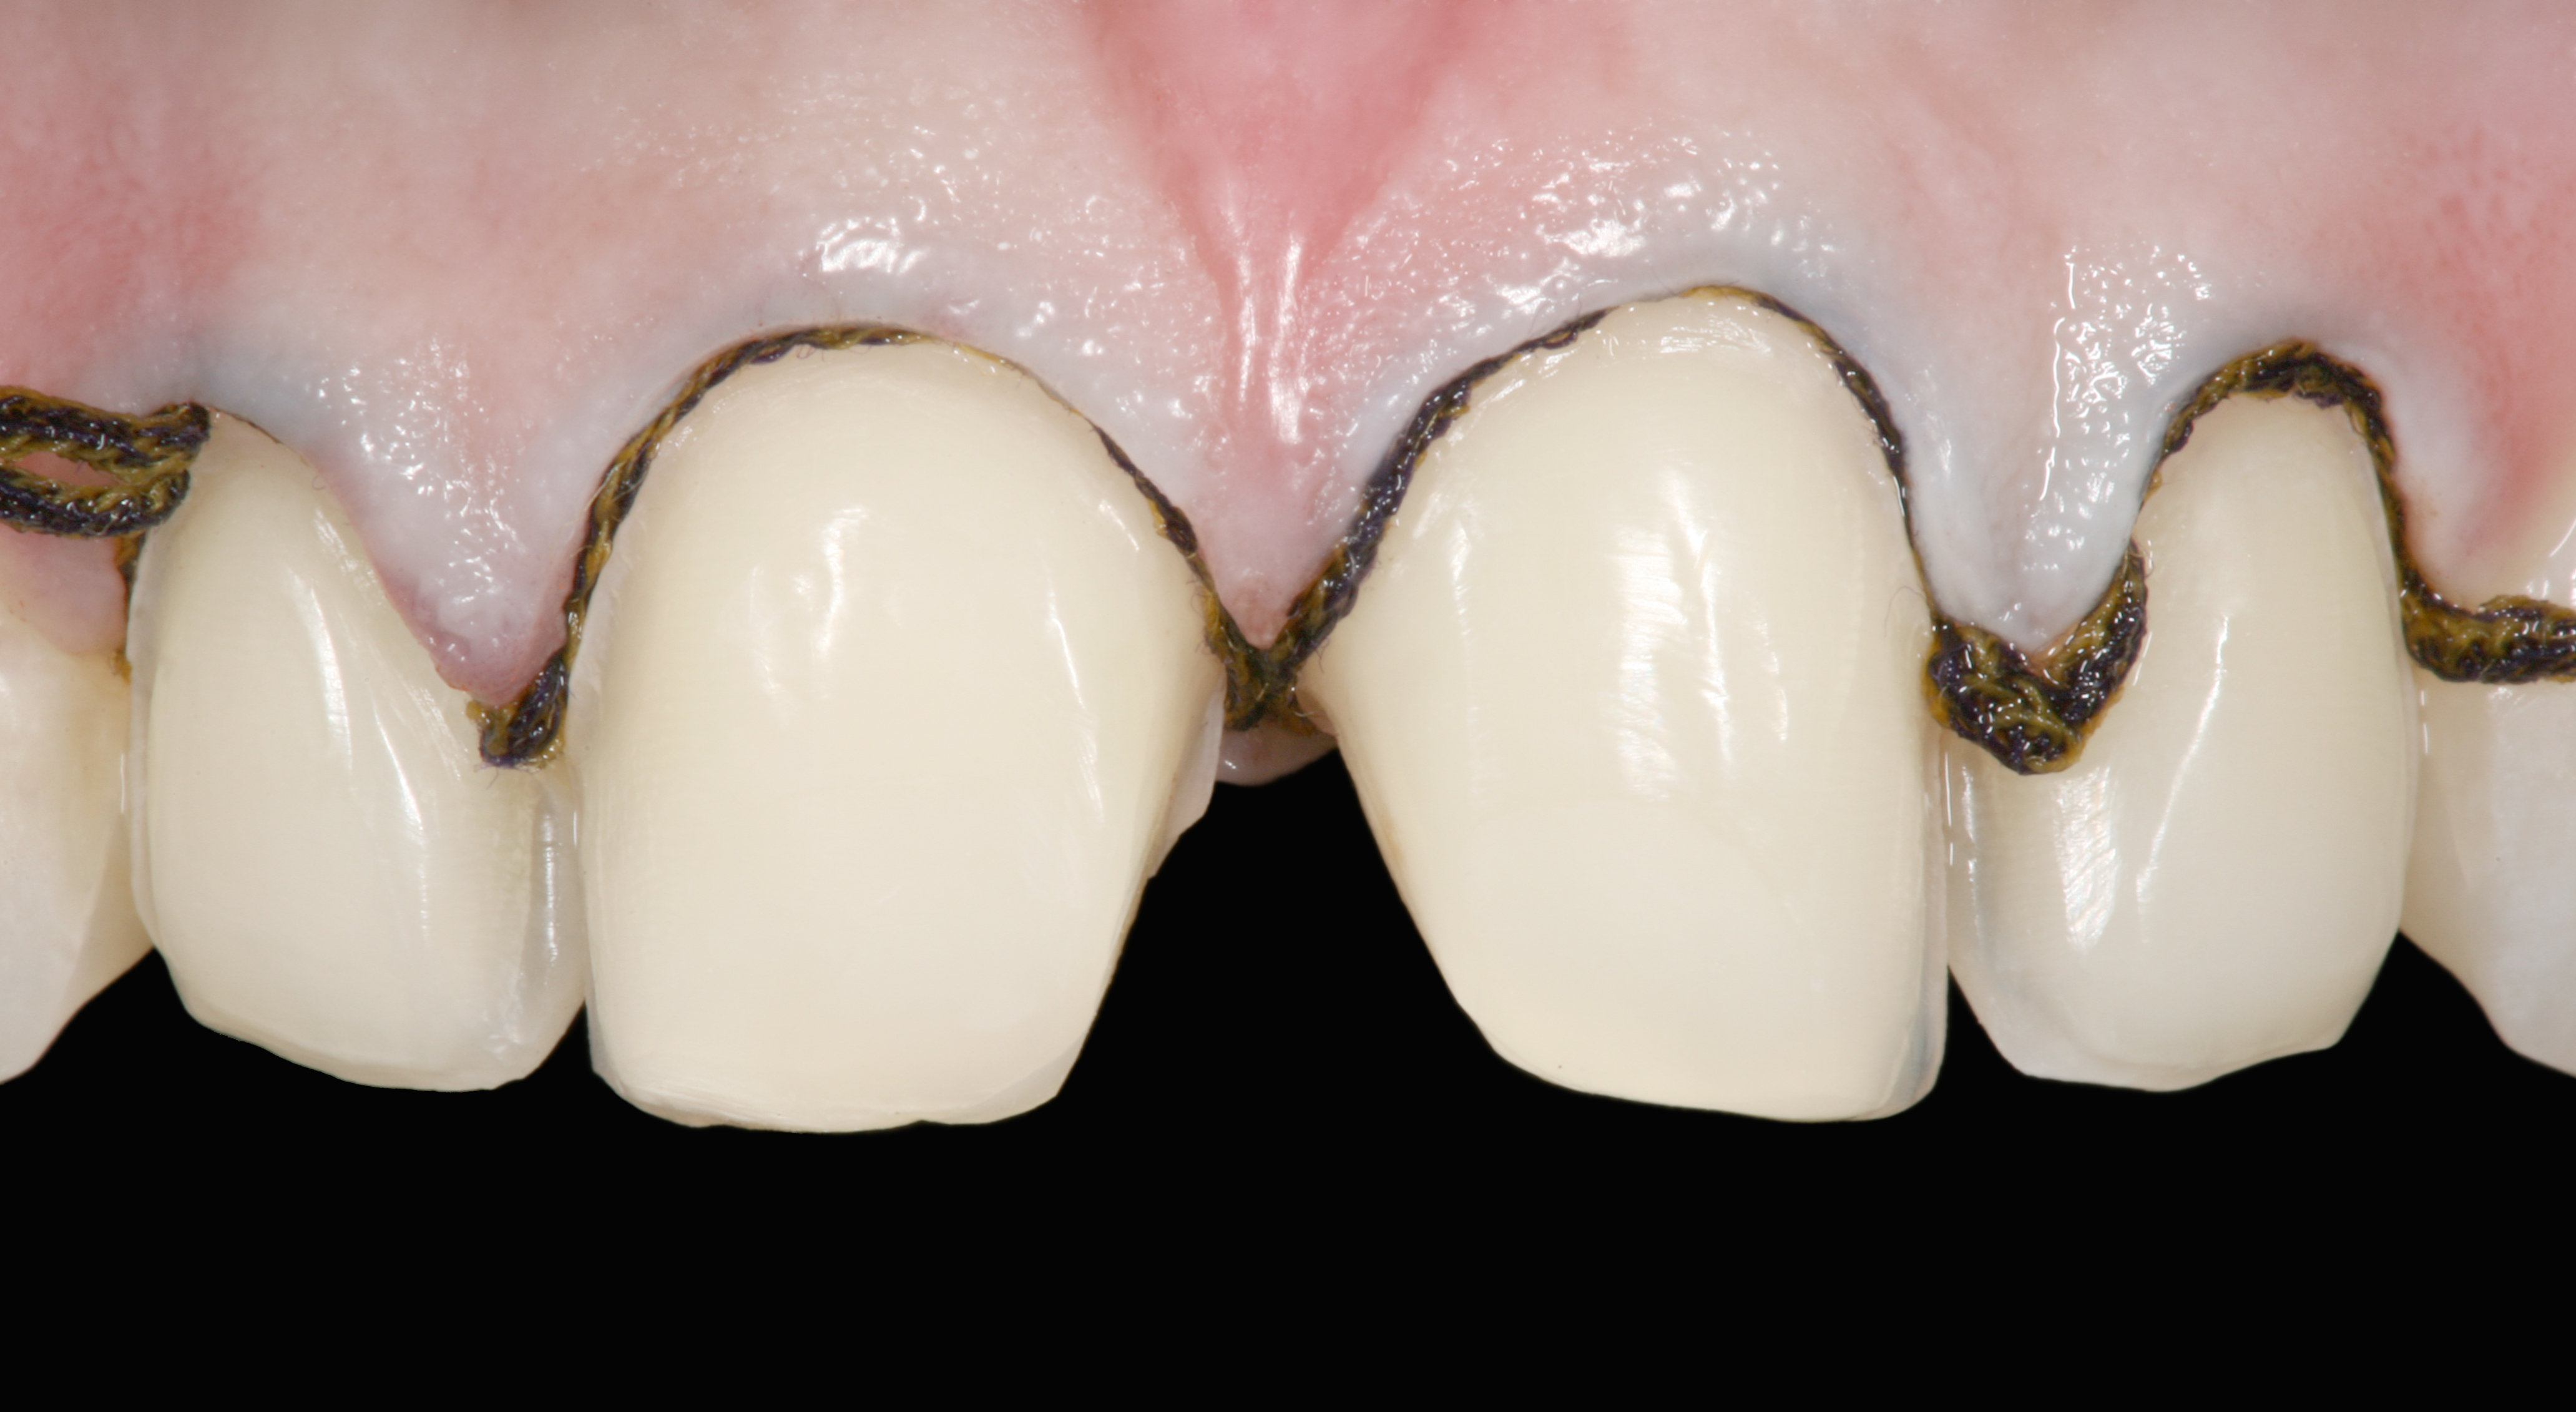

The clinical application of this protocol is illustrated in a patient situation where laminate veneers were placed on four maxillary incisors to replace lost tooth structure and restore function and esthetics. The failing restorations were removed, followed by a conservative veneer preparation (Figure 1 and Figure 2). The bonding surfaces of the feldspathic porcelain veneers were acid-etched with hydrofluoric acid for 2 minutes (Figure 3) and thoroughly rinsed. Then a silane coupling agent was applied (Figure 4). Figure 5 demonstrates the situation after bonding the veneers to the teeth with a composite resin luting agent.

The pretreatment situation.

Figure 1